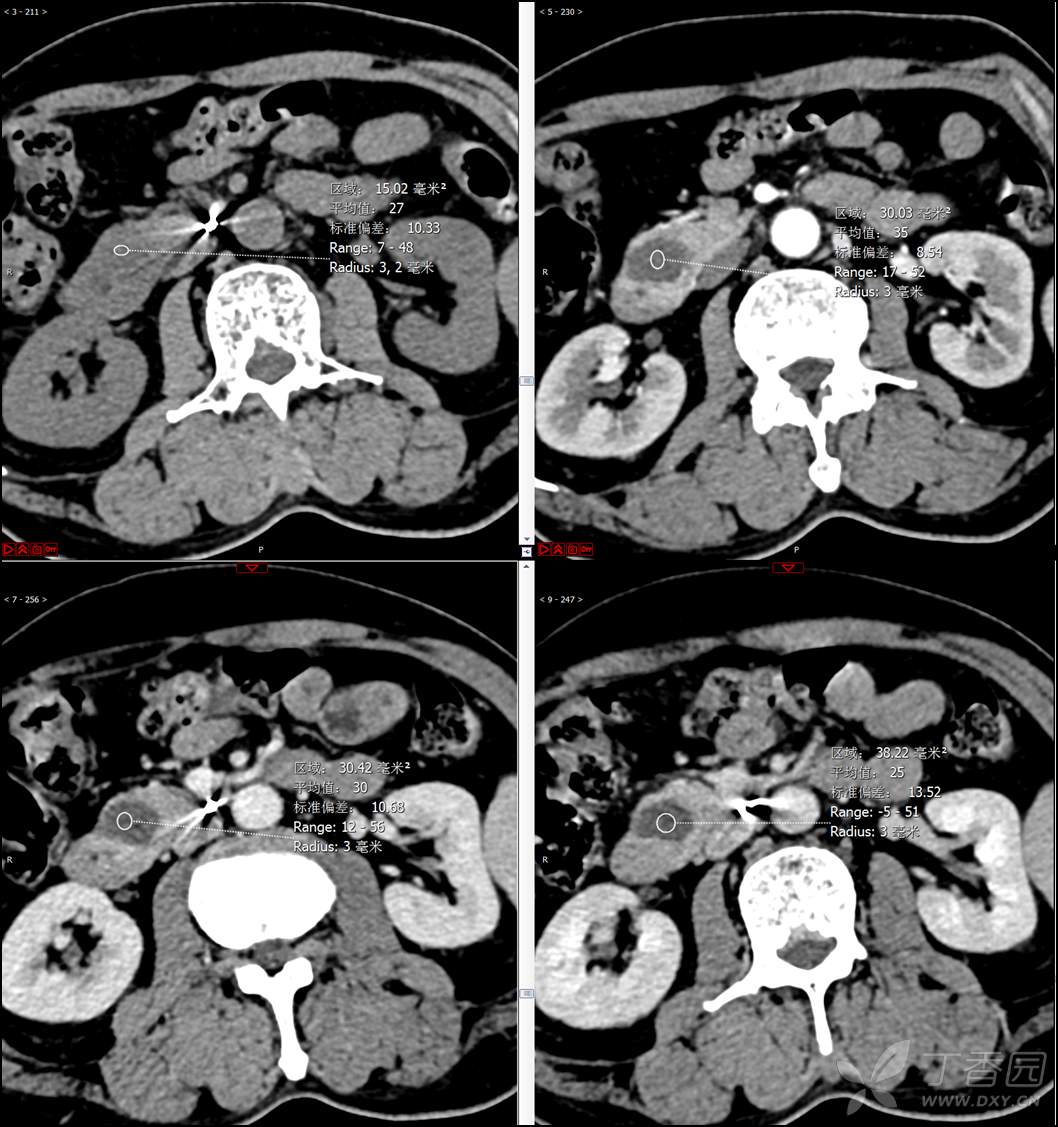

【影诊笔记521】老年男性,黑便就诊,请分析~『回帖即可查阅答案』

患者年龄:67岁

主诉:黑便1周。

现病史:患者1周前无明显诱因出现黑便伴头晕、心慌,无胸闷、胸痛,后仍间断黑便,2022-10-27就诊于某市中医院,行胃镜检查示:十二指肠溃疡伴出血,给予止血、抑酸等对症治疗,效果欠佳。今为行进一步治疗就诊于我院急诊,门诊完善新型冠状病毒核酸检测后以“十二指肠溃疡伴出血”收入我科。患者自发病以来,神志清,精神可,未进食,睡眠可,小便未见异常,黑便,近期体重无明显增减。